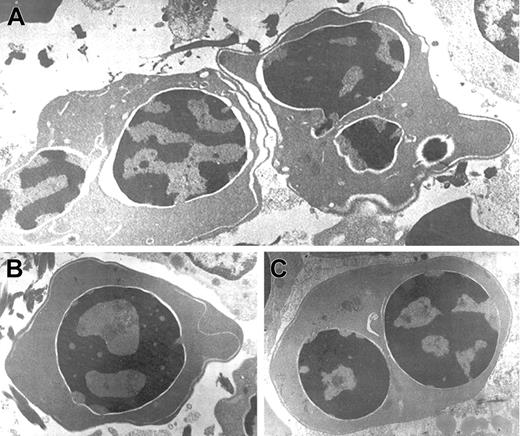

Electron microscopic aberrations were more prominent in late erythroblasts (Figure 2). The nuclear outline was often undulated or lobulated, and the nuclear membrane–associated heterochromatin was frequently absent over large areas of the nuclear membrane. In some cells, the heterochromatin was spongy and showed numerous “punched out” areas. The main cytoplasmic anomaly was the presence of abundant cytoplasmic membranes that are composed of excessive smooth endoplasmic reticulum. These characteristic cisternae usually ran parallel beneath the cell outer membrane producing the so-called “double membrane.” The dilatation of the space between the 2 layers of these cytoplasmic membranes was frequently observed, as was the dilatation of the space of the nuclear membrane.

Electron micrographs of several bone marrow late erythroblasts.

Multinucleate erythroblasts showing striking “double membranes” with partial dilatation of the intramembranous space (A). Erythroblasts revealing nondilated cisternae (B,C). Late erythroblast depicting spongy heterochromatin with numerous “punched out” areas (B). Binucleate erythroblasts showing large areas of nuclear membrane without attached heterochromatin (C). Uranyl acetate and lead citrate stain. Original magnification: A, × 10 600; B and C, × 18 000).